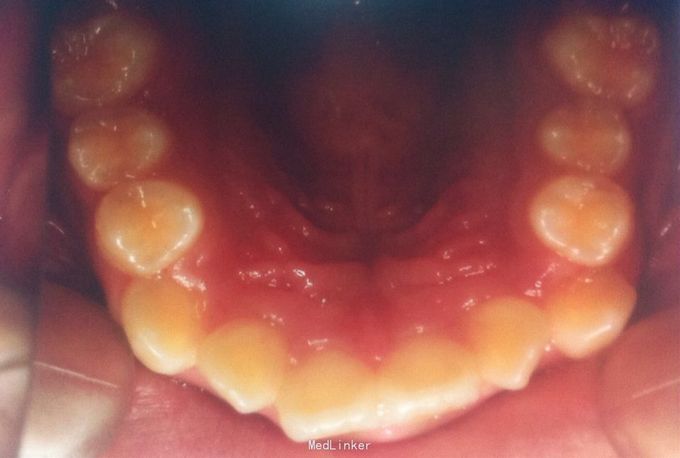

恒牙期 33,44唇侧错位 磨牙中性关系 前牙覆合2度、覆盖1度 牙列拥挤

牙列拥挤、安氏一类 拔牙矫治,拔除14、24、34、44(强支抗)排齐整平上下牙列,直丝弓矫治器,关闭拔牙间隙,矫治后前牙覆合覆盖正常,磨牙中性关系,面型略改善